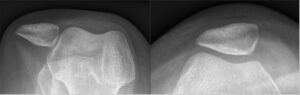

Kniescheibe/Patella

Eine Patellaluxation bezeichnet eine Verletzung, bei der die Kniescheibe (Patella) aus ihrer natürlichen Position im femoralen Gleitlager (Trochlea) herausrutscht

- Anatomische Veränderungen: Abweichungen in der knöchernen Struktur, X-Beine (Valgus), eine zu flach ausgeprägte Führungsrinne (Trochlea) können dazu führen, dass die Patella leichter luxiert. Meist ist es eine Kombination aus verschiedenen Risikofaktoren.

- Bildgebende Verfahren: Röntgenaufnahmen, Magnetresonanztomographie (MRT)